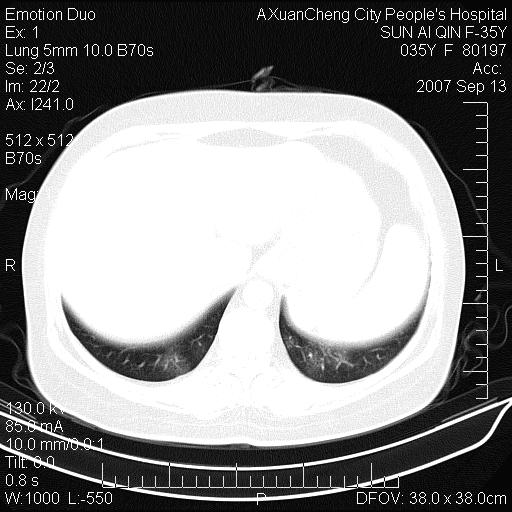

以下是引用天南地北在2007-9-13 13:43:00的发言:[br]考虑双肺、肺门侵润

以下是引用ydx_74在2007-9-13 15:42:00的发言:[br]仅看片,考虑右上肺癌并双肺转移,结合病史,考虑肺门、肺内淋巴侵润

以下是引用同在2007-9-13 15:08:00的发言:[br]支持肺门及双肺侵润.